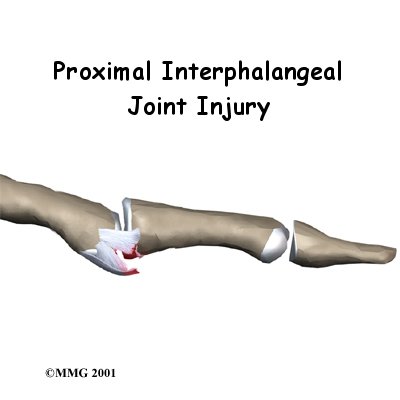

PIP Joint Injuries of the Finger

We use our hands constantly, placing them in harm's way continuously.Injuries to the finger joints are common and usually heal without significant problems. Some injuries are more serious and may develop problems if not treated carefully. One such injury is a sprain of the proximal interphalangeal joint, or PIP joint, of the finger. This joint is one of the most unforgiving joints in the body to injury. What appears at first to be a simple sprain of the PIP joint may result in a painful and stif...